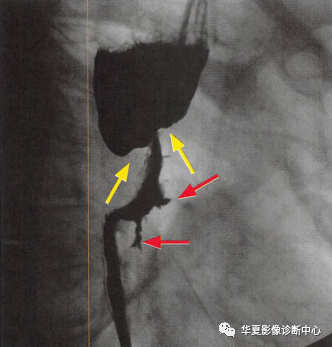

食管癌在鋇餐造影下的一種表現之一,顯示食管局部不規則狹窄(黃箭頭:玫瑰花花干),近端食管擴張(萎陷的玫瑰花朵),兩個不規則線狀潰瘍(紅箭頭:玫瑰花葉/刺),形似黑色玫瑰花,小編原創命名為:“黑色玫瑰花征”,幫助記憶,加深映像